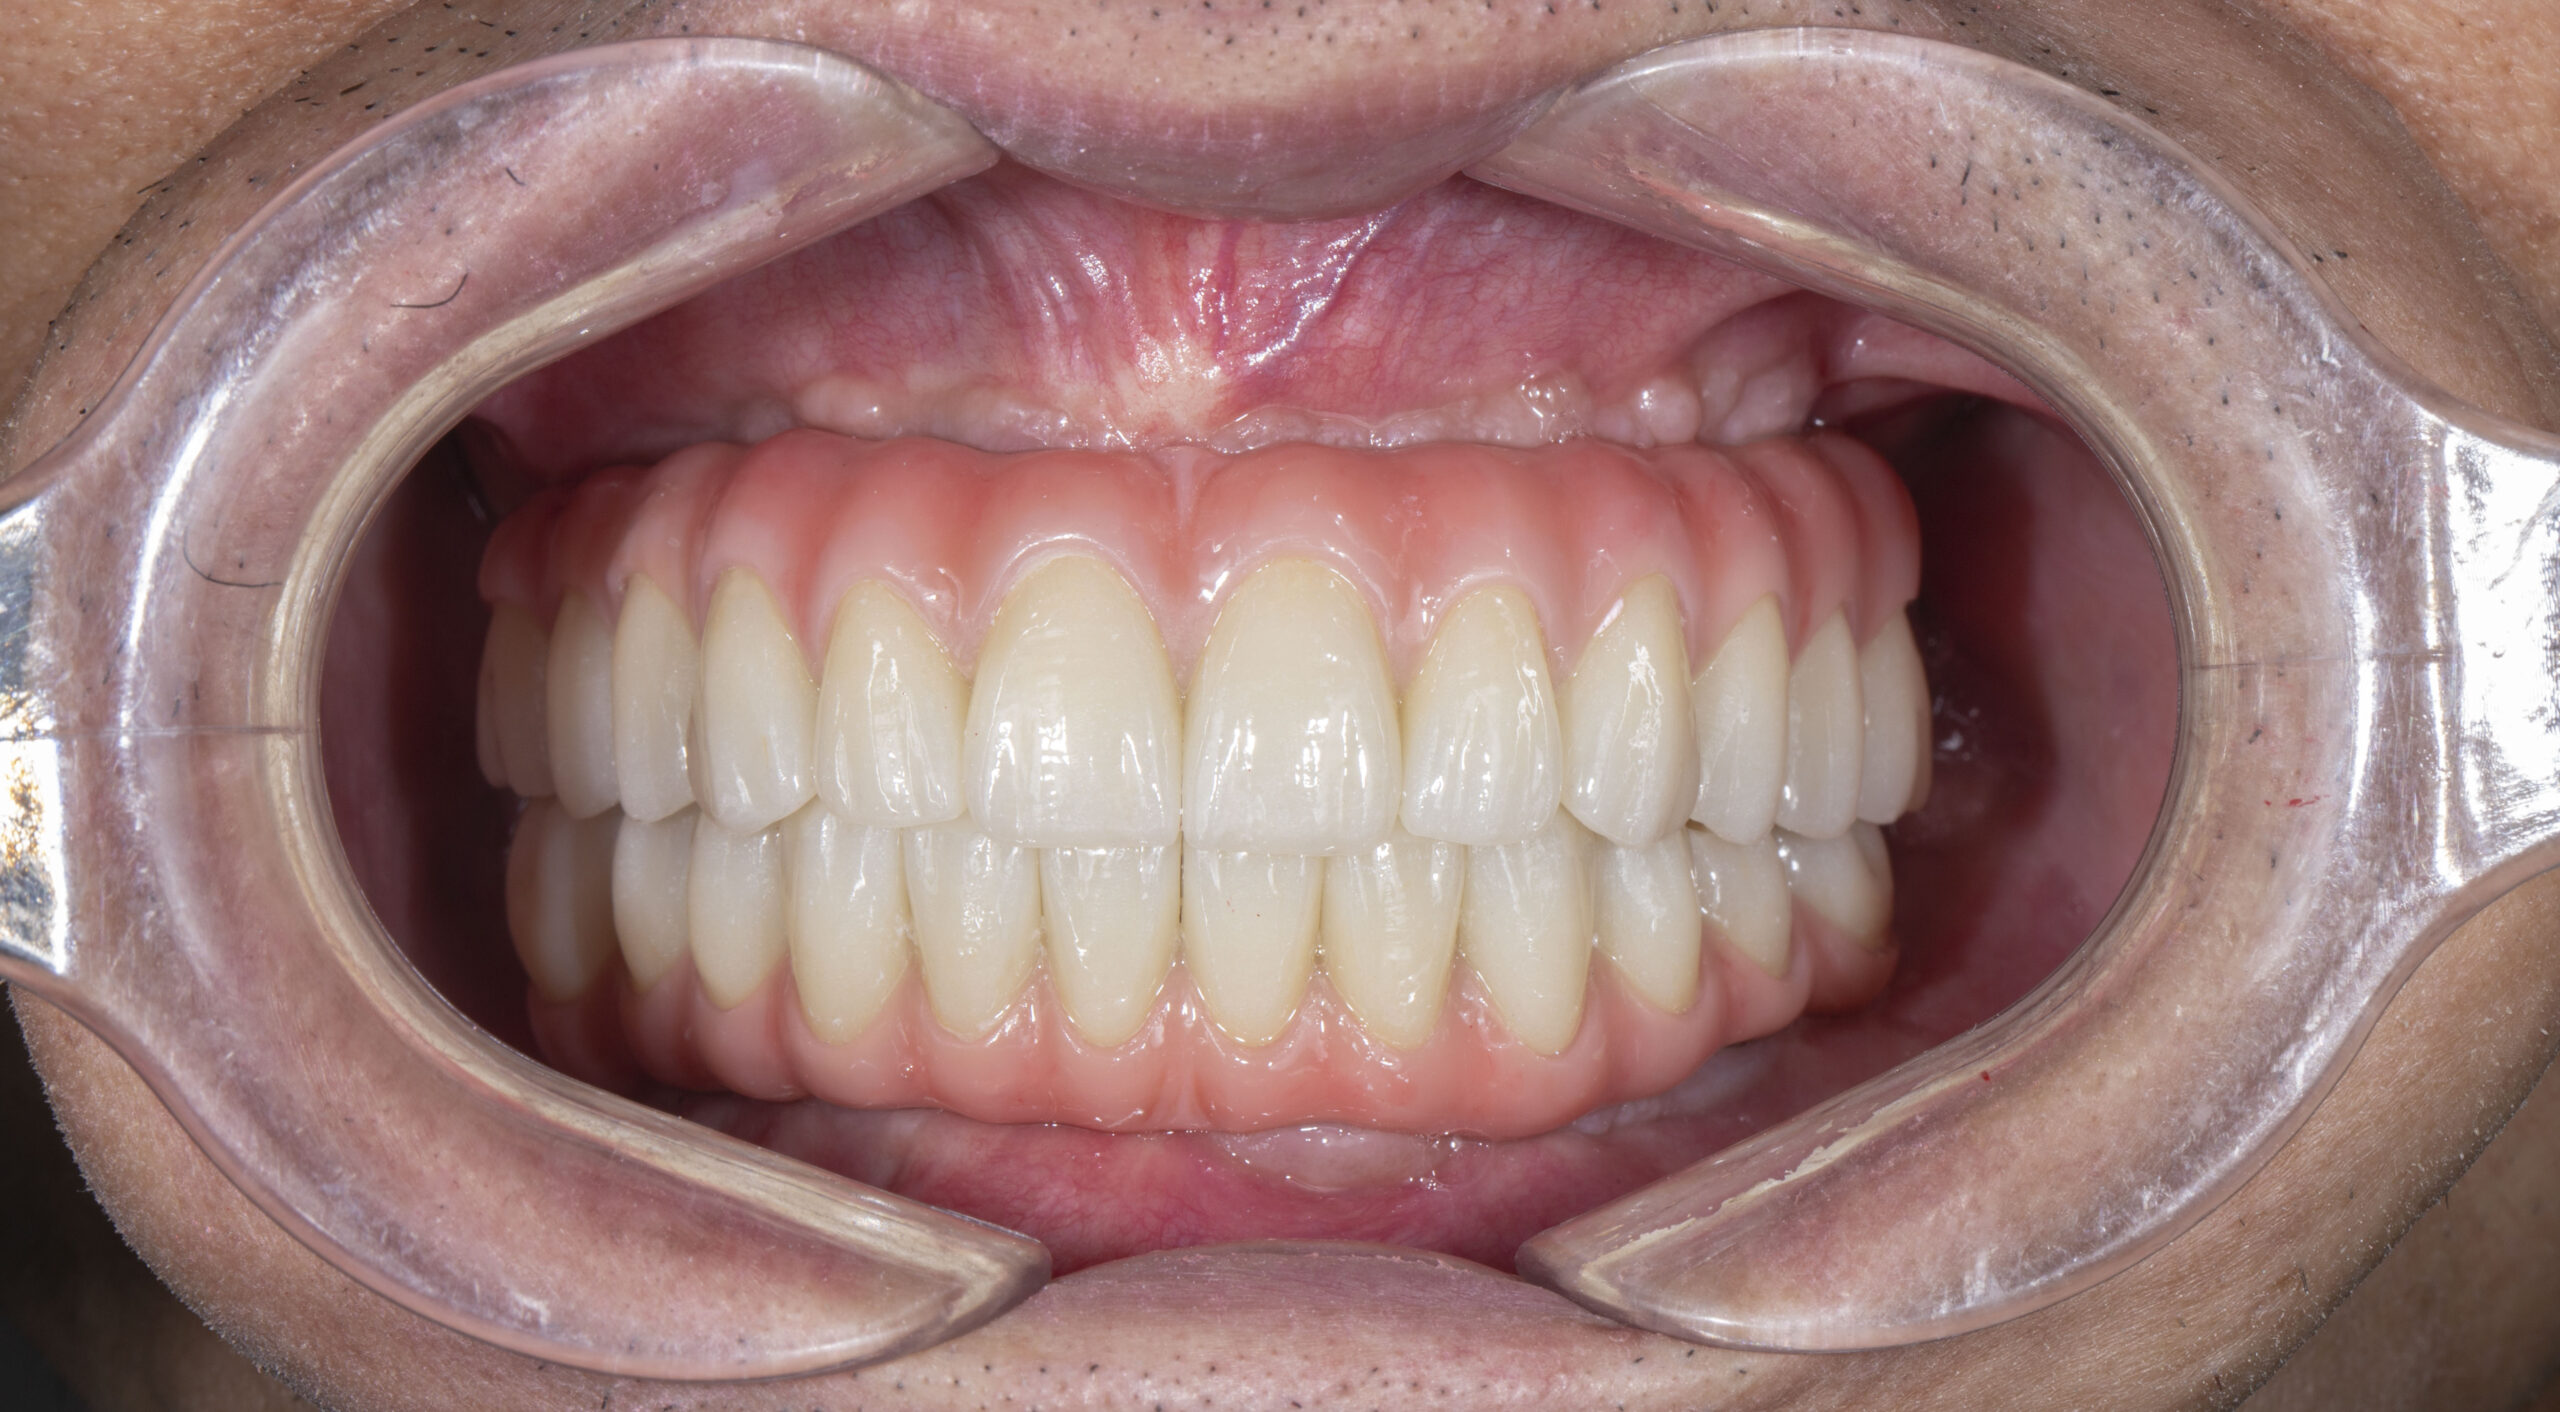

Trường hợp mất răng của cô Nguyễn Kim Hoa (64 tuổi; Hoàn Kiếm- Hà Nội); Trồng Implant toàn hàm dưới

Kế hoạch điều trị:

+ Chia thành 2 đợt điều trị cấy toàn hàm dưới trước

+ Trồng răng toàn hàm dưới 6 trụ Neodent của Thụy Sỹ: 22,5 Triệu x 6 = 135 Triệu

+ Làm hàm sứ rời Zirconia 12 răng: 54 Triệu

Tổng chi phí điều trị trồng răng toàn hàm trên: 135 Triệu + 54 triệu = 189 Triệu